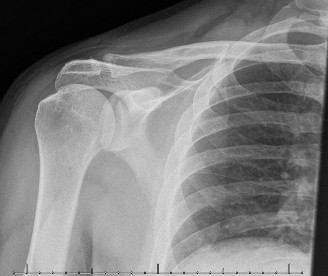

Rotator cuff tears are a common reason for shoulder pain and a common reason to obtain shoulder imaging. As a result, numerous different imaging modalities exist offering different pros and cons. Plain films are still the initial imaging modality of choice. These are most useful in ruling out other possible diagnosis but can help with the diagnosis of a rotator cuff tear as well. Changes to the tendon itself

may appear as calcific tendinosis, which would most commonly be seen at the bone–tendon interface. A decrease in the acromiohumeral distance (less than 2 mm) may also be indicative of a cuff tear. In late cases of rotator cuff tears, superior subluxation of the humerus may be evident. Certain variations in acromial anatomy, including spurs or a hook-shaped (type 3) acromions, may be associated with rotator cuff tears as well. With progression of rotator cuff tears, degenerative changes including spurs, cysts, and sclerosis may be evident at the greater tuberosity. In late, massive tears one may see degenerative changes consistent with rotator cuff arthropathy.

A high riding humeral head on plain films (Answer A) is associated with a massive rotator cuff tear and is the first sign of progression to cuff tear arthropathy that is seen on plain film.

It should be noted that reverse total shoulder arthroplasty is also the procedure of choice in patients with cuff-tear arthropathy (aka rotator cuff arthropathy). Characteristics of cuff-tear arthropathy include superior migration of the humerus due to a massive rotator cuff tear, glenohumeral joint destruction, subchondral osteoporosis, and humeral head collapse (see Fig. 2–17). A reverse total shoulder